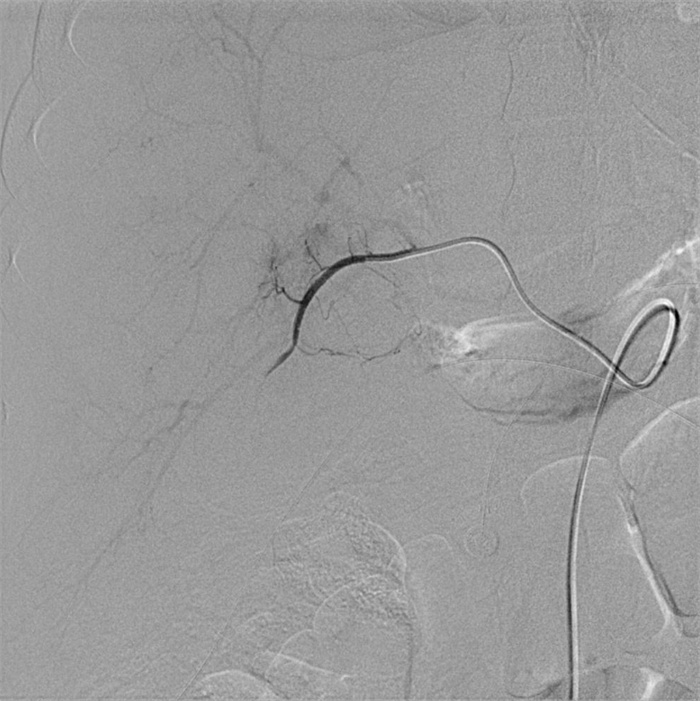

入院第57天,患者再次出现暗红色血便,伴阵发性右上腹痛,无发热、呕血,症状与之前相同。鉴于患者有活动性出血,再次复查胃镜:慢性浅表性胃炎伴糜烂。复查肝功能:γ-GT 844 U/L,TBil 43.6 μmol/L,NCBil 16.6 μmol/L,CBil 27 μmol/L,肝功指标再次回升,γ-GT、CBil明显升高,提示可能出现胆道梗阻。肝胆脾胰腺彩超复查:胆囊肿大、胆囊陈旧性稠厚淤胆(较前无明显变化),胰腺稍大并不均质改变。复查上腹CT:AP复查情况与之前相同,可能有胆囊出血(见图 2)。联合介入放射科行血管造影检查,常规局部麻醉下采用Seldinger技术由右侧股动脉入路,造影发现胆囊动脉分支出血(图 3),超选择胆囊动脉分支用明胶海绵颗粒行栓塞止血(图 4)。同时,行经皮经肝胆囊穿刺置管引流(图 5),病情稳定后带管出院,3月后予以拔除,择期行胆囊切除。

| 胆囊动脉增粗,其分支局部造影剂外溢,未见明显动脉瘤征象 图 3 胆囊动脉造影 |

| 栓后造影胆囊动脉主干以远闭塞,造影剂外溢征象消失 图 4 胆囊动脉介入栓塞术后复查造影 |

回顾总结该病例,不难发现,患者病程中两次活动性出血有共同点:先间断性右上腹痛,继之便血,伴γ-GT、CBil指标异常升高,以及胆囊内出现疑似结石、出血的影像学改变。胆囊内出血经胆道排出后,在十二指肠处可见少量新鲜血液,故首次胃镜检查时,根据十二指肠球部少量新鲜血迹判断球部炎症存在一定的误诊。另外,特别需要强调的是,少量的出血混合胆汁在影像学检查上表现为疑似新发的胆囊结石,临床不应直接考虑为胆囊淤胆性结石,尤其急性SAP患者出现上诉临床特征时,应当考虑胆囊动脉出血的可能性。直至患者第二次便血后,再次组织多学科会诊联合介入放射科进一步行血管造影,发现并确定胆囊动脉出血,但未见明显动脉瘤征象,行胆囊动脉栓塞后患者出血停止。

胆囊动脉出血是罕见的胰腺炎血管并发症,确切的病理基础尚不清楚,推测其出血的机制主要继发于胰管释放的胰酶侵蚀及炎症刺激损伤血管壁[4]。介入放射科的共同参与在复杂胰腺炎的救治中有着重要作用[8],胆囊动脉出血难以被常规的检查发现,尤其是经常规治疗后患者仍有活动性出血时,选择性血管造影应作为首选方法。血管造影仍然是目前判断有无活动性出血的“金标准”,敏感度可达80%~90%以上[9]。血管造影同时发现异常血管、急性出血病因及部位[10],发现病灶的同时可给予介入治疗,有助于迅速维持血流动力学稳定。